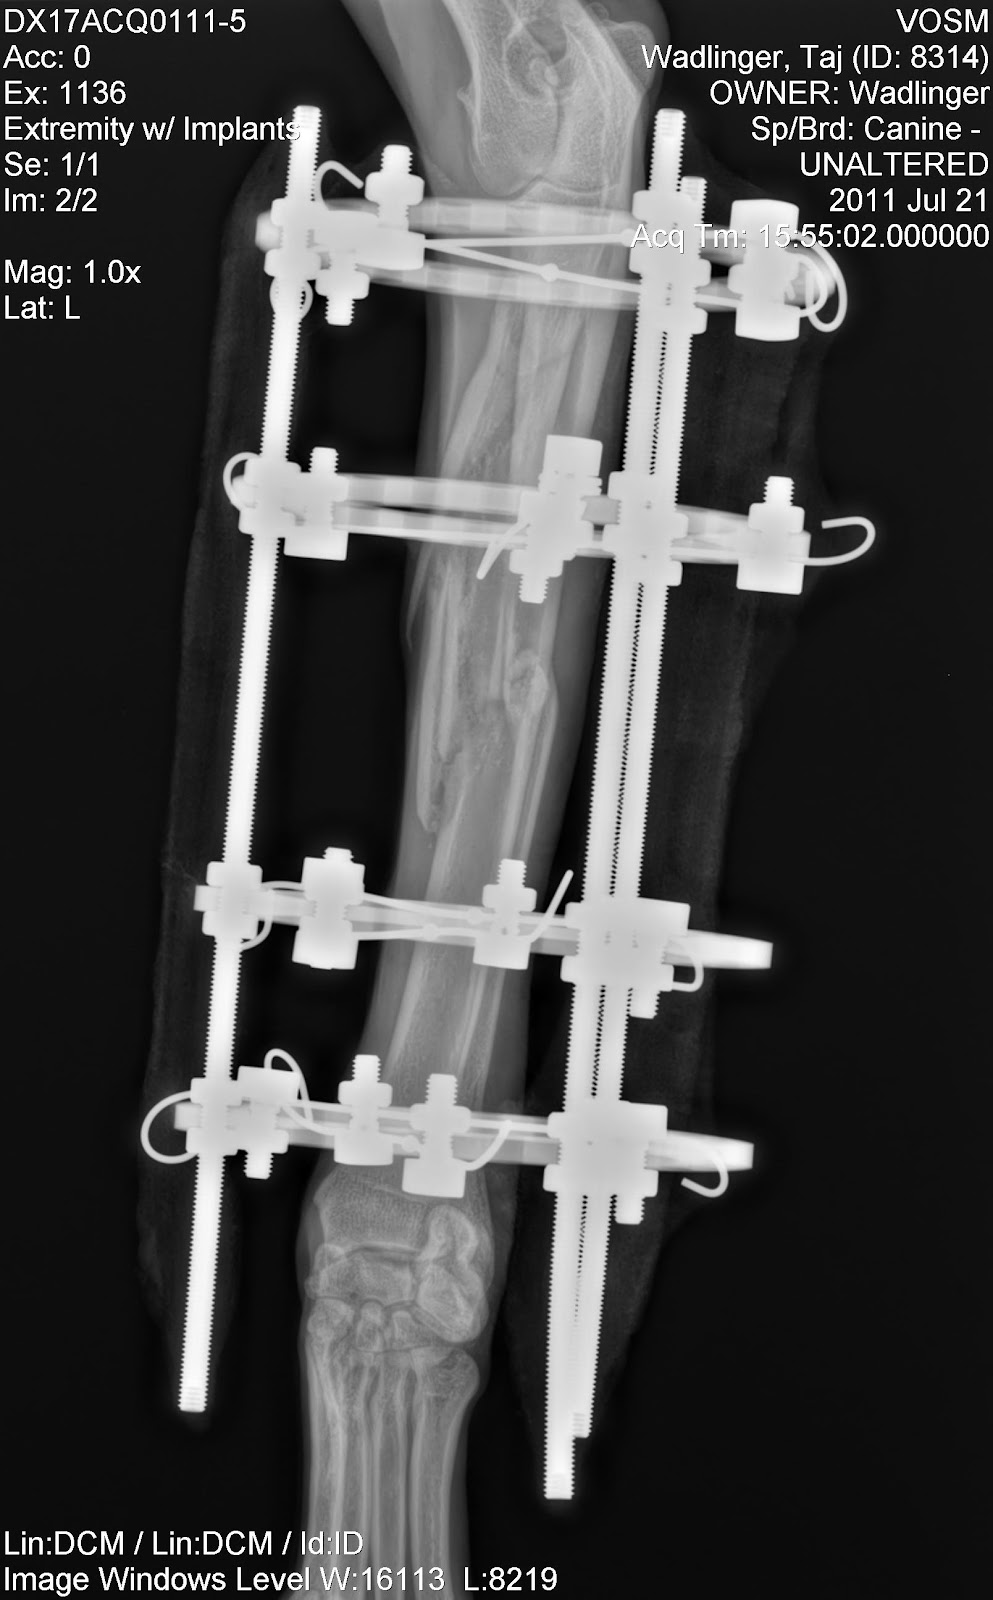

Post-surgery:

Post-operative radiographs confirmed appropriate implant positioning and good anatomic alignment (elbow over wrist). Perfect reduction was not attempted due to the severe comminuted nature of the fracture. Perfect positioning of the bone fragments is not necessary, and clinical studies have shown that disturbing a break with internal surgery can sometimes: slow the healing process by disturbing the fracture hematoma and periosteal blood supply, cause longer surgery times, heighten risk for infection and blood loss, cause higher levels of post-op pain, and possibly more post-surgical complications (Dudley et al.,

J Am Vet Med Assoc., 1997; Johnson et al,

J Am Vet Med Assoc., 1998; Ozsoy & Altunatmaz,

Vet Med Czech, 2003; Schmal et al.,

J Orthop Trauma, 2011).

| Lateral View: Post Fixator Surgery |

Front to Back View:

Post Fixator Surgery |